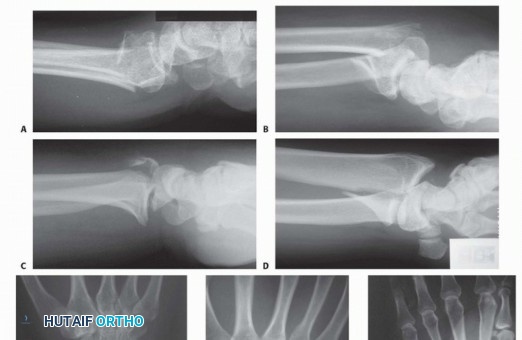

### FIG 3 • Pathogenesis of dorsal radius fractures. A. Dorsal bending. B. Volar bending. C. Dorsal shear. D. Volar shear. E. Radial shear. F. Three-part articular. G. Comminuted articular. H. Carpal avulsion. I. High energy. 78 Dorsal shearing injuries present as fractures of the dorsal rim and are often associated with dorsal instability of the carpus ( FIG 3C). These injuries often have a depressed articular fragment and may have additional radial column involvement. Volar shearing injuries present as displaced fractures of the volar rim and result in volar instability of the carpus ( FIG 3D). This pattern often has multiple articular fragments and is highly unstable. It is not usually amenable to closed methods of treatment. Radial shearing fractures (chauffeur's fracture) are identified by a characteristic transverse fracture line across the radial styloid that extends into the radiocarpal joint. These injuries often have more extensive chondral disruption than may be appreciated from the radiographic findings ( FIG 3E). Simple three-part fractures are usually the result of lowenergy injuries that combine a dorsal bending mechanism with some axial loading across the carpus ( FIG 3F). This pattern is characterized by the presence of an ulnar corner fragment involving the dorsal portion of the sigmoid notch, a main articular fragment, and a proximal shaft fragment. Complex articular fractures are usually the result of axial loading injuries from moderate to high-energy trauma. In addition to articular comminution, this pattern may often generate a significant defect in the metaphyseal cavity or complete disruption of the DRUJ ( FIG 3G). The avulsion/carpal instability pattern is primarily a ligamentous injury of the carpus with associated osseous avulsions of the distal radius. Bone fragments are typically small and very distal ( FIG 3H).

### FIG 4 • A. Positioning for standard lateral radiography. B. Standard lateral radiograph. C. Positioning for 10-degree lateral radiography. D. Ten-degree lateral radiograph. Note the improved visualization of the articular surface of the base of the scaphoid facet and the entire lunate facet. Injuries from a high-energy mechanism present as complex comminuted fractures of the articular surface with extension into the radial/ulnar shaft ( FIG 3I). ## IMAGING AND OTHER DIAGNOSTIC STUDIES Posteroanterior (PA), standard lateral ( FIG 4A,B), and 10-degree lateral views are routine views for radiographic evaluation of the distal radius. The 10-degree lateral view (FIG 4C,D) clearly visualizes the ulnar two-thirds of the articular surface from the base of the scaphoid facet through the entire lunate facet. Oblique views may also be helpful for evaluating the injury. The radiographic features of distal radius fractures include the following 8: Carpal facet horizon ( FIG 5A,B). This is the radiodense horizontal landmark that is used to identify the volar and dorsal rim on the PA view. If the articular surface has palmar tilt, the x-ray beam is tangential to the subchondral bone of the volar portion of the lunate facet, with the result that the carpal facet horizon identifies the volar rim. However, if the articular surface has displaced into dorsal tilt, the x-ray beam becomes tangential to the subchondral bone of the dorsal portion of the lunate facet instead, and the carpal facet horizon identifies the dorsal rim (not shown). The carpal facet horizon corresponds to the portion of the articular surface visualized on the 10-degree lateral x-ray projection. Teardrop angle (normal 70 ± 5 degrees; FIG 5C,D). The teardrop angle is used to identify dorsiflexion of the volar 79 rim of the lunate facet. Depression of the teardrop angle to a value less than 45 degrees indicates that the volar rim of the lunate facet has rotated dorsally and impacted into the metaphyseal cavity (axial instability pattern of the volar rim). This may be associated with axial and dorsal subluxation of the carpus. Restoration of the teardrop angle is necessary to correct this type of malreduction.